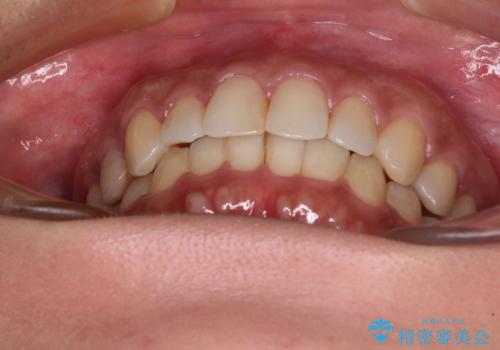

沖縄から飛行機で通院 インビザラインによる矯正治療

- 30代女性

- インビザライン

- 3年8ヶ月

- 定期的に東京に来るので、沖縄から矯正治療で通院したいとのことで来院された患者様です。

歯列不正は軽度であったので、応急処置の少ないインビザラインにて矯正治療を行うこととしました。

通院途中に、仕事の都合で東京に来る機会が激減してしまったため、なかなか治療が進まず、当初終了予定であった時期が2年近くずれ込んでしまいました。